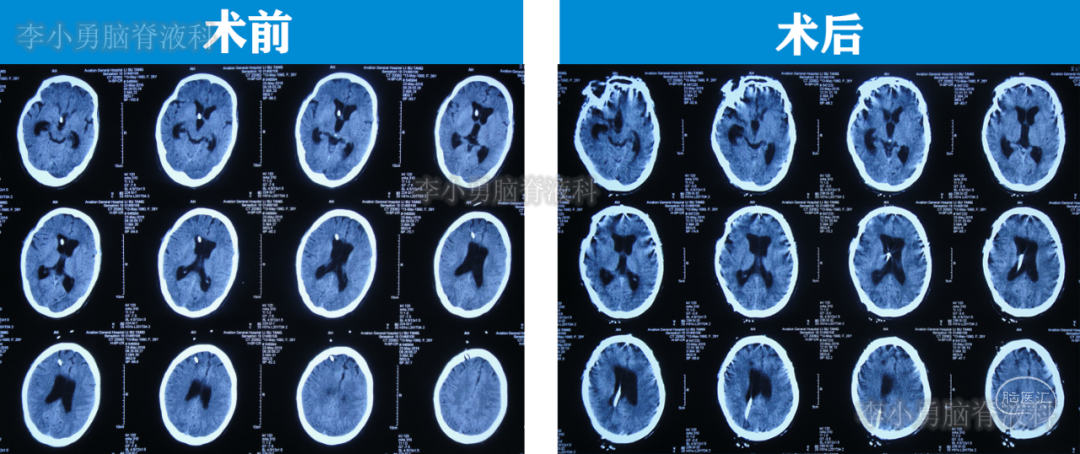

2017年4月21日(住院治疗11个月)出院,出院时:由入院时卧床,意识模糊改善为:能坐轮椅,意识清楚;由入院时不能遵嘱动作,全身震颤好转为:四肢能遵嘱动作,肢体震颤减轻,但嘴角震颤消失;由入院时吞咽困难好转为能经口进食;但双脚仍呈“芭蕾舞脚”,不能言语交流,发出的"嗯嗯"声基本消失,睁闭眼变正常(图-33)。出院前2017年4月18日查头颅CT示未见异常(图-34)。

图-34:2017年4月18日头颅CT